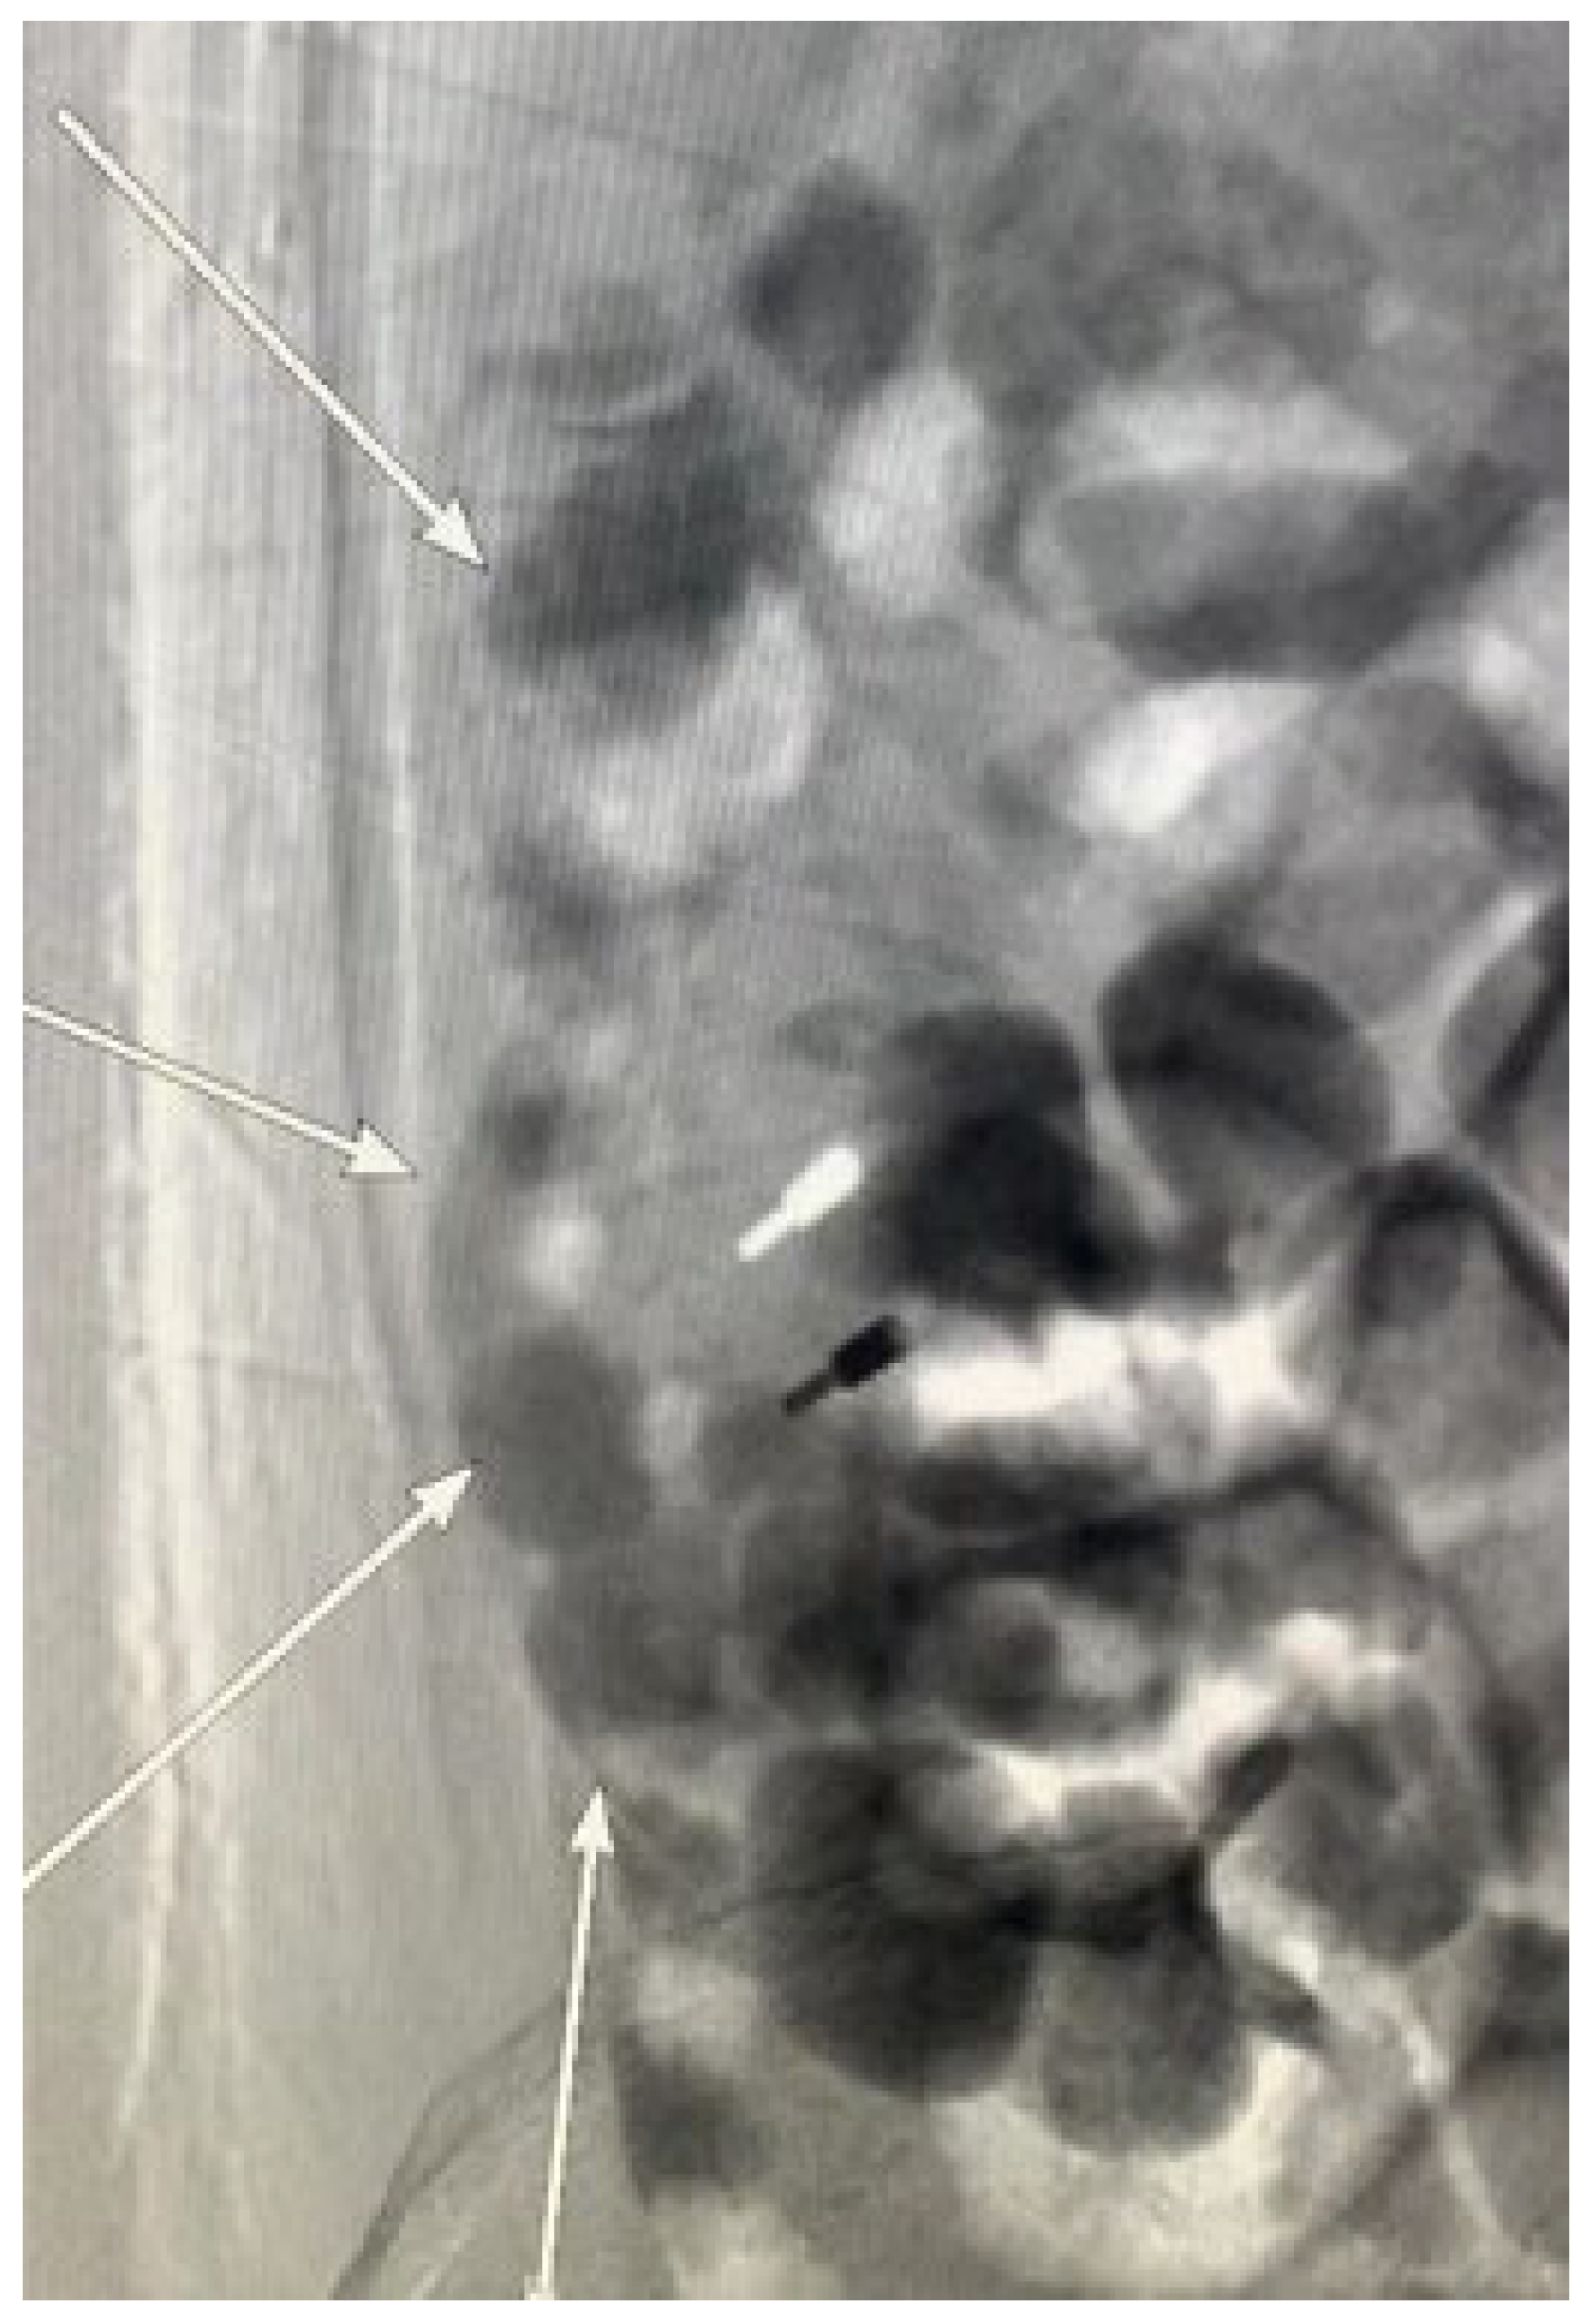

During the colonoscopy, a titanium clip was placed to achieve temporary hemostasis and provide time for vascular embolization under interventional radiology. Venography via the inferior vena cava performed to determine the extent of vascular involvement for embolization revealed multiple varicose veins in the ascending colon draining into the inferior vena cava (the white arrows). Due to the extensive variceal involvement and the high risk of congestion and necrosis following embolization, the vascular embolization procedure was discontinued. A multidisciplinary team evaluated the case; based on liver function, portal hypertension severity, and the condition of the varices, they recommended a transjugular intrahepatic portosystemic shunt (TIPS) procedure. The patient and their family declined this option, choosing instead to return to their local hospital for further management. Despite the interventions, the prognosis remained poor, with a significant risk of rebleeding due to decompensated liver cirrhosis, severe hepatic dysfunction, and extensive varices. The patient was advised to consult a specialized hepatic center for evaluation and potential liver transplantation. Six months later, during a follow-up phone call, the patient’s family reported that his condition was stable but declined to allow direct communication with the patient. Due to the lack of robust evidence-based treatment options for colonic variceal bleeding, the management of this patient was largely based on clinical experience and the medical resources available at our hospital. If varices are luminally accessible and stigmata of active or recent hemorrhage (i.e., white nipple and red signs) are present, first-line treatment should be endoscopic, either elastic band ligation (EBL) or endoscopic cyanoacrylate injection [2]. EBL has been successfully and safely used for managing duodenal and rectal variceal hemorrhage [3,4], although risk of rebleeding can arise depending on the location, size, and accessibility of the varices, with some reports of a 40% rebleeding rate in patients with rectal varices [5]. Endoscopic cyanoacrylate injection is also effective in achieving hemostasis and preventing rebleeding in duodenal varices, with good long-term outcomes. However, studies regarding its use in colorectal varices is still limited [6]. Endoscopic ultrasound-guided (EUS) therapies, including EUS-guided cyanoacrylate injection [7] and coil embolization [8] are emerging as important tools for variceal management. Coil embolization, in particular, can provide a scaffold for injecting smaller volumes of cyanoacrylate glue in a combined approach. These techniques offer significant advantages, including real-time Doppler assessment of variceal flow and the ability to identify varices that may not be visible via mucosal inspection. However, the current application of EUS-guided variceal interventions is largely limited to duodenal [9] or rectal varices [10,11], with only limited reports on their use for proximal colonic varices.